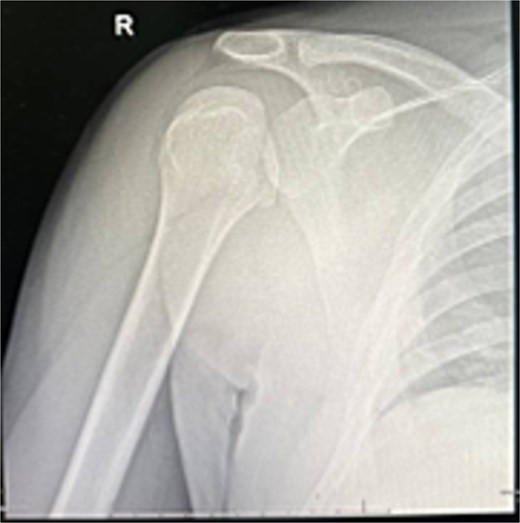

A 31-year-old male with sickle cell disease presented to the emergency department after an electrical shock caused him to fall onto the back of his shoulder. He developed severe pain and inability to use his arm. Examination revealed the shoulder in adduction and internal rotation with marked limitation of flexion and external rotation. X-rays showed posterior shoulder dislocation with a non-displaced proximal humerus fracture (Fig. 1). The injury was overlooked, and he was discharged in an arm sling.